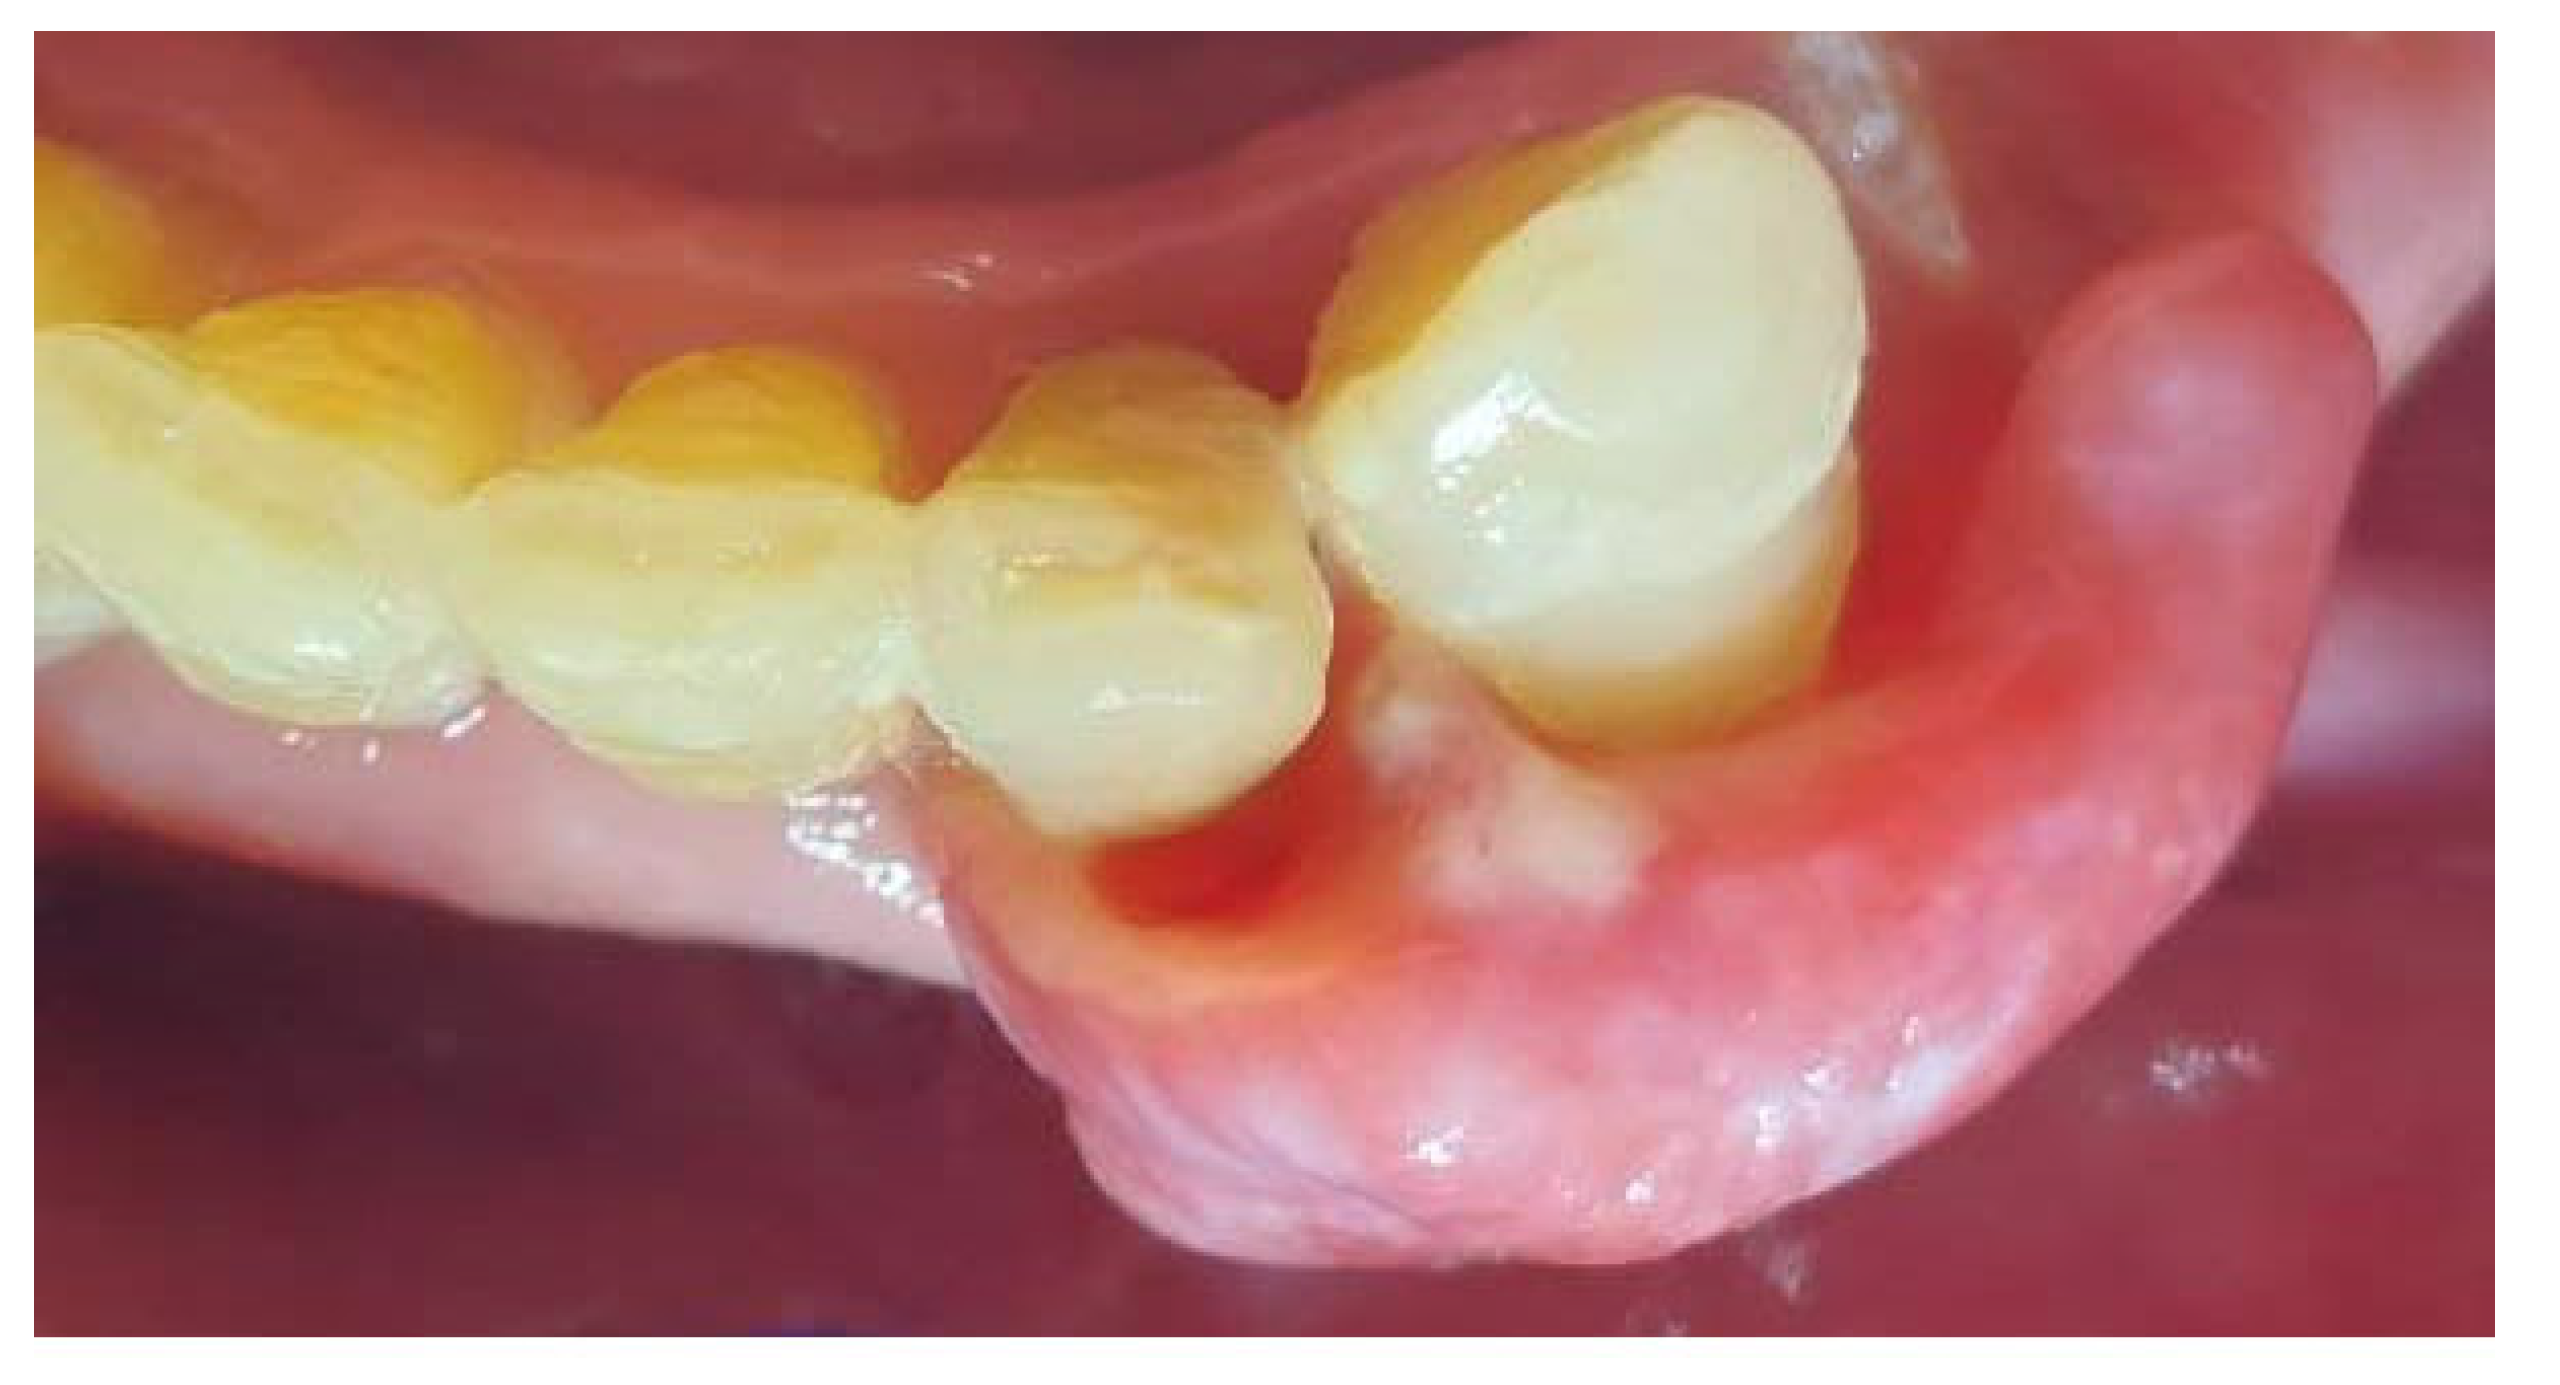

On the day of presentation to the Department of Oral Surgery, the extraoral examination noted painless, enlarged submandibular lymph nodes on the left side. Intraoral examination revealed the presence of gingival tumors in the area of teeth 17-16 (Figure 1a) and 32-33 (Figure 2 and Figure 3). The lesions were pedunculated, with a narrow pedicle, elastic-hard, irregularly elliptical in shape with impressions of adjacent teeth, pink in color with local hyperemia and white spots. They arose from the marginal gingiva, which was swollen and protruding. The patient had active periodontal disease. The maxillary tumor measured 22 x 10 x 5 mm, the mandibular tumor 30 x 20 x 6 mm and was in close proximity to the teeth. The periodontium was inflamed with the presence of pathological pockets and plaque deposits. Teeth 17, 16, 33 showed grade II mobility. Residual roots of teeth 34, 35 were present. The panoramic radiograph did not show any abnormalities in the bone structure of the tumor area. The patient underwent professional hygiene before surgical treatment due to abundant plaque deposits. Clinically, the image corresponded to reactive hyperplastic lesions, resembling fibrous hyperplasia or pyogenic granuloma.

Figure 2. Mandibular tumor in the area of teeth 32-33.